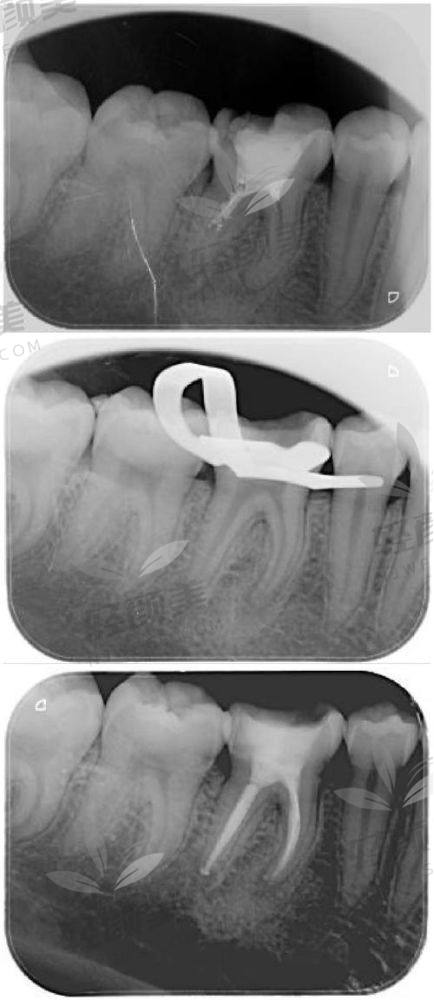

根管治疗的核心目的是清除感染的牙髓组织,防止进一步扩散,保住牙根结构——这是让你牙齿“假死而不拔”的高阶“急救操作”!

根管治疗什么时候做更合适?讲真,有几个明显信号一出现,就别再等了:

✔️ 龋齿越过界线 → 龋坏深入牙髓,牙神经都吓冒烟,不处理分分钟发展成根尖周炎。

✔️ 牙齿变色(灰黑/暗黄) → 特别可能牙髓已经坏死,继续放任等于是“僵尸牙”挂号排队。

✔️ 外力撞击 → 就算牙齿表面没崩,也可能内部已经髓腔受伤,早做检查,早发现、早处理。

✔️ 牙龈反复长包流脓 → 根尖囊肿的预警信号之一,别靠吃几颗消炎药糊弄过去!

✔️ 冷热刺激已久 → 牙神经已经持续受伤敏感,这是牙髓的“求救短信”!